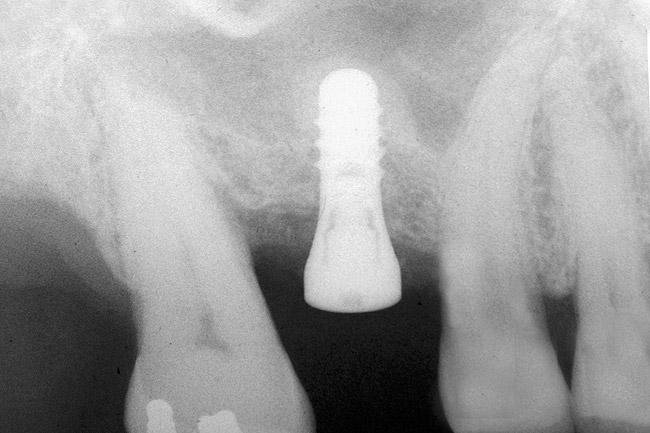

After penetration into the sinus is achieved, a sterile amalgam carrier is used two times to deliver a radiopaque bone substitute into the osteotomy. Then the osteotome used to infracture the subantral floor is lubricated with saline and inserted into the osteotomy until the stop on the osteotome reaches the alveolar crest. This pushes the bone substitute up under the sinus membrane and elevates it. Two more carriers of bone substitute are delivered in the same manner. This will provide around 2 mm of bone height in the sinus (four carriers provide around 2 mm of bone height). A radiograph is then taken to verify that the membrane was elevated, and the bone graft should appear as a dome (Figure 4). If the sinus floor has not been penetrated despite the impression that it was, the bone-graft material may have been pushed laterally. If this occurs, there will be no dome on the radiograph, but, rather, increased osseous density on the lateral aspect of the osteotomy. If this occurs the osteotomy needs to be deepened.

Figure 4  After infracturing the subantral wall with a 3.5-mm osteotome, bone was added and the presence of a dome was confirmed with a radiograph.

Figure 4

Figure 6  At site No. 14, a radiograph depicting the full "dome" of graft material apical to the implant.

Figure 6

Figure 7  Radiograph depicting a "flattening" of the dome that has taken place in the first year after the graft was performed. This shows consolidation of the graft and remodeling that takes place over time.

Figure 7